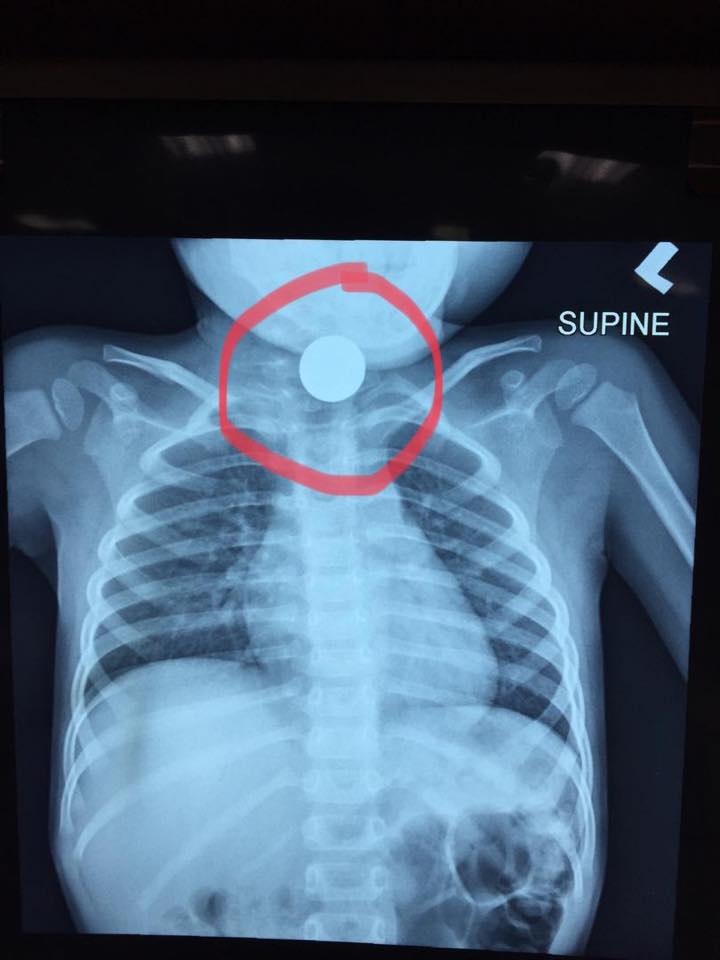

Reza và bố mẹ em phải đợi thêm 1 giờ đồng hồ để nhận được kết quả chụp X-quang. Kết quả cho thấy có một đồng xu 20 cent bị mắc kẹt giữa đường hô hấp và thực quản của em.

Phim X-quang cho thấy có một đồng xu kẹt giữa đường hô hấp và thực quản của cậu bé ( Ảnh: Facebook)